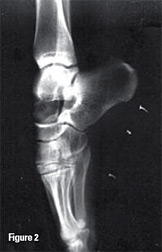

Figure 2: Foot X-ray showing extreme plantarflexion in a ballet dancer while en pointe.

PAIS in the presence of an os trigonum may be associated with additional irritation of the synchondrosis, causing the development of secondary inflammatory tissue that may perpetuate the cycle of impingement and inflammation. PAIS is common in ballet dancers, but is also encountered in those who participate in other sports that involve forced plantarflexion of the foot, such as soccer, basketball, and volleyball.1